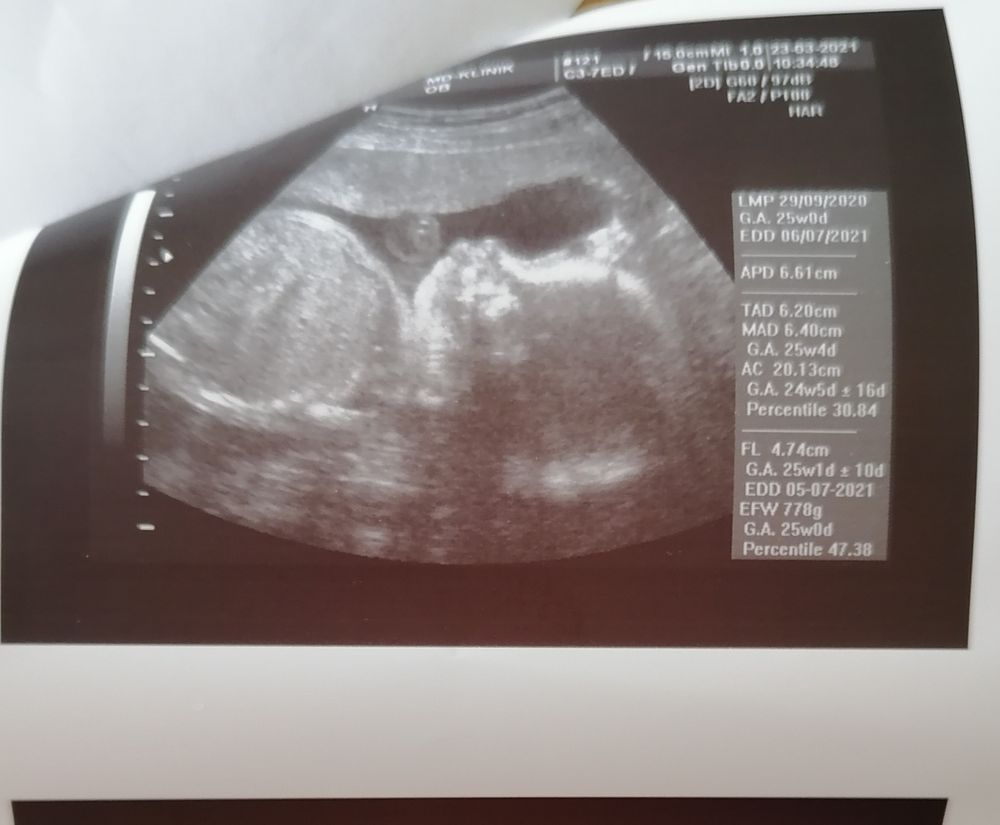

Результаты узи

Сынулька тттт растёт и с ним все хорошо. Кровоток в зоне С, печень в норме, шевелится сильно. Весит уже 850гр.